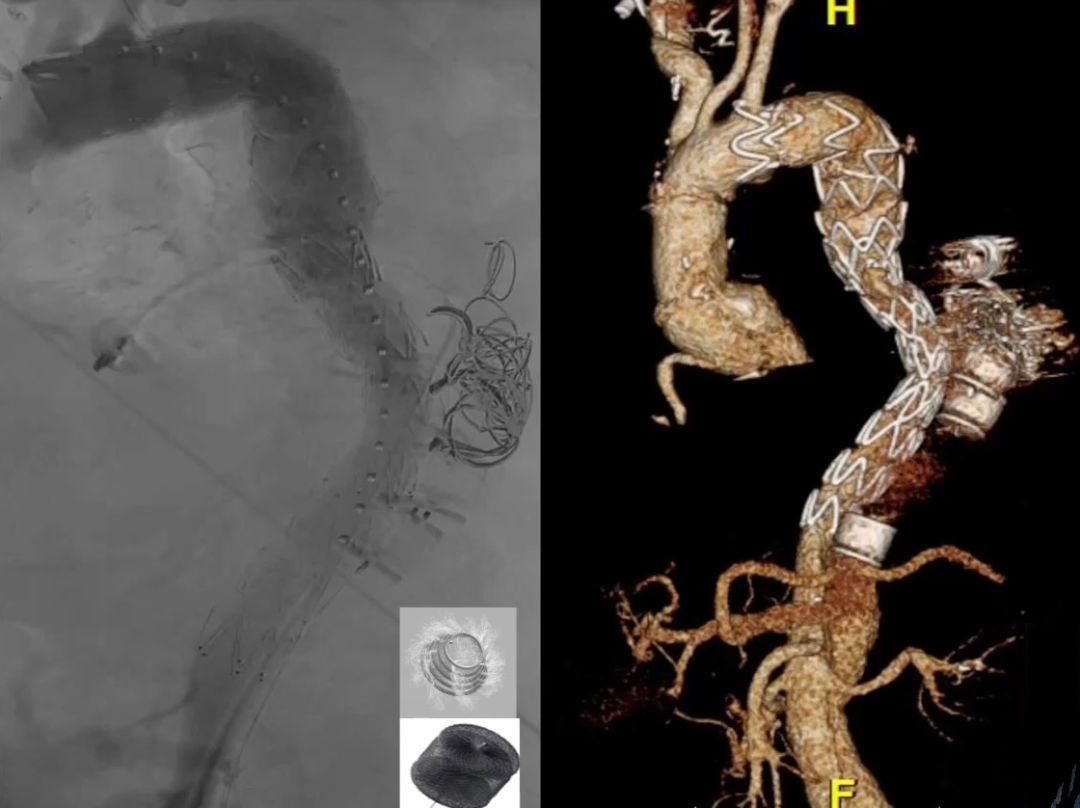

Candy-plug如下图所示,是一种特制的血管塞,将袖套(cuff)进行改造,然后用血管塞塞住进行输送,并封闭血管塞的金属部分,这种材料是可以商业化生产的。

可以看到下图中有一个COOK的产品,这种产品在欧洲上市,但是在美国并没有。Candy-plug内部的尺寸比假腔的平均直径大10%~30%,在腹腔干上方1cm处与真腔内的支架平行放置,随后将假腔封堵住。

1、前期准备:使用16mm GORE的Viabahn支架,裁剪至合适长度后,在器械台上安装到袖套上,缝合到位,随后回装入输送系统,在指定位置释放。(相对于缝合设计,此方法能有一个更稳定和更耐用的Candy-plug设计(包裹的糖果)。前者容易导致在中心处破裂和释放,重新封装后,可以直接输送Candy-plug);

GORE 16mm Viabahn

2、下图为病例的影像图,可以看到支架的位置,受到压迫的真腔位置就在此处,通过影像图可以看到这里出现了内漏,必须进行处理;

3、进入假腔后可以看到真假腔中都有一根导丝。我们就可以将预先制作的Candy-plug沿导丝送入假腔。Candy-plug与支架保持平行,向上进入,将Candy-plug在这里释放;

4、我们需要在置入处放置22mm血管塞,放置位置需要准确及牢固。之后对真腔进行球囊后扩张,以此确保支架能够获得良好的封闭效果。

手术结果

术后造影及CT显示良好的真腔形态,假腔无返流,手术结果满意。

(术后造影图)

(术后CTA图)

达到了手术目的,恢复正常真腔血流且阻断假腔远端返血,促进血栓化。